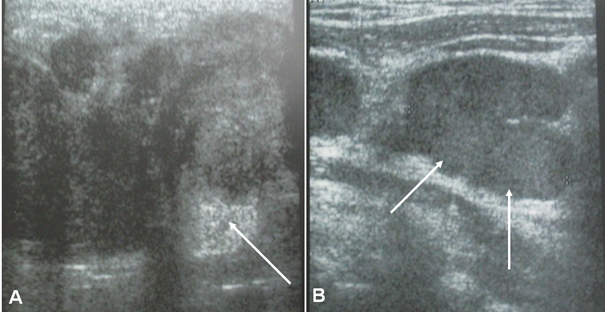

Parotid ultrasound showed an enlarged parotid with a heterogeneous tumor, poorly defined, and hyper vascularized on Doppler, associated with multiple satellite adenopathies (Figure 1). Computed tomography (CT) scan showed a parotid swollen by a parenchymal tumor, hypodense, heterogeneous, and enhancing heterogeneously after injection of contrast product. This tumor infiltrated the peri-parotid fat with multiple adenopathies of secondary appearance (Figure 2 & 3).

Figure 2 Axial CT scans of the parotid gland, without contrast: Parenchymal, hypodense, and heterogeneous tumor of the left parotid gland with multiple adenopathies.